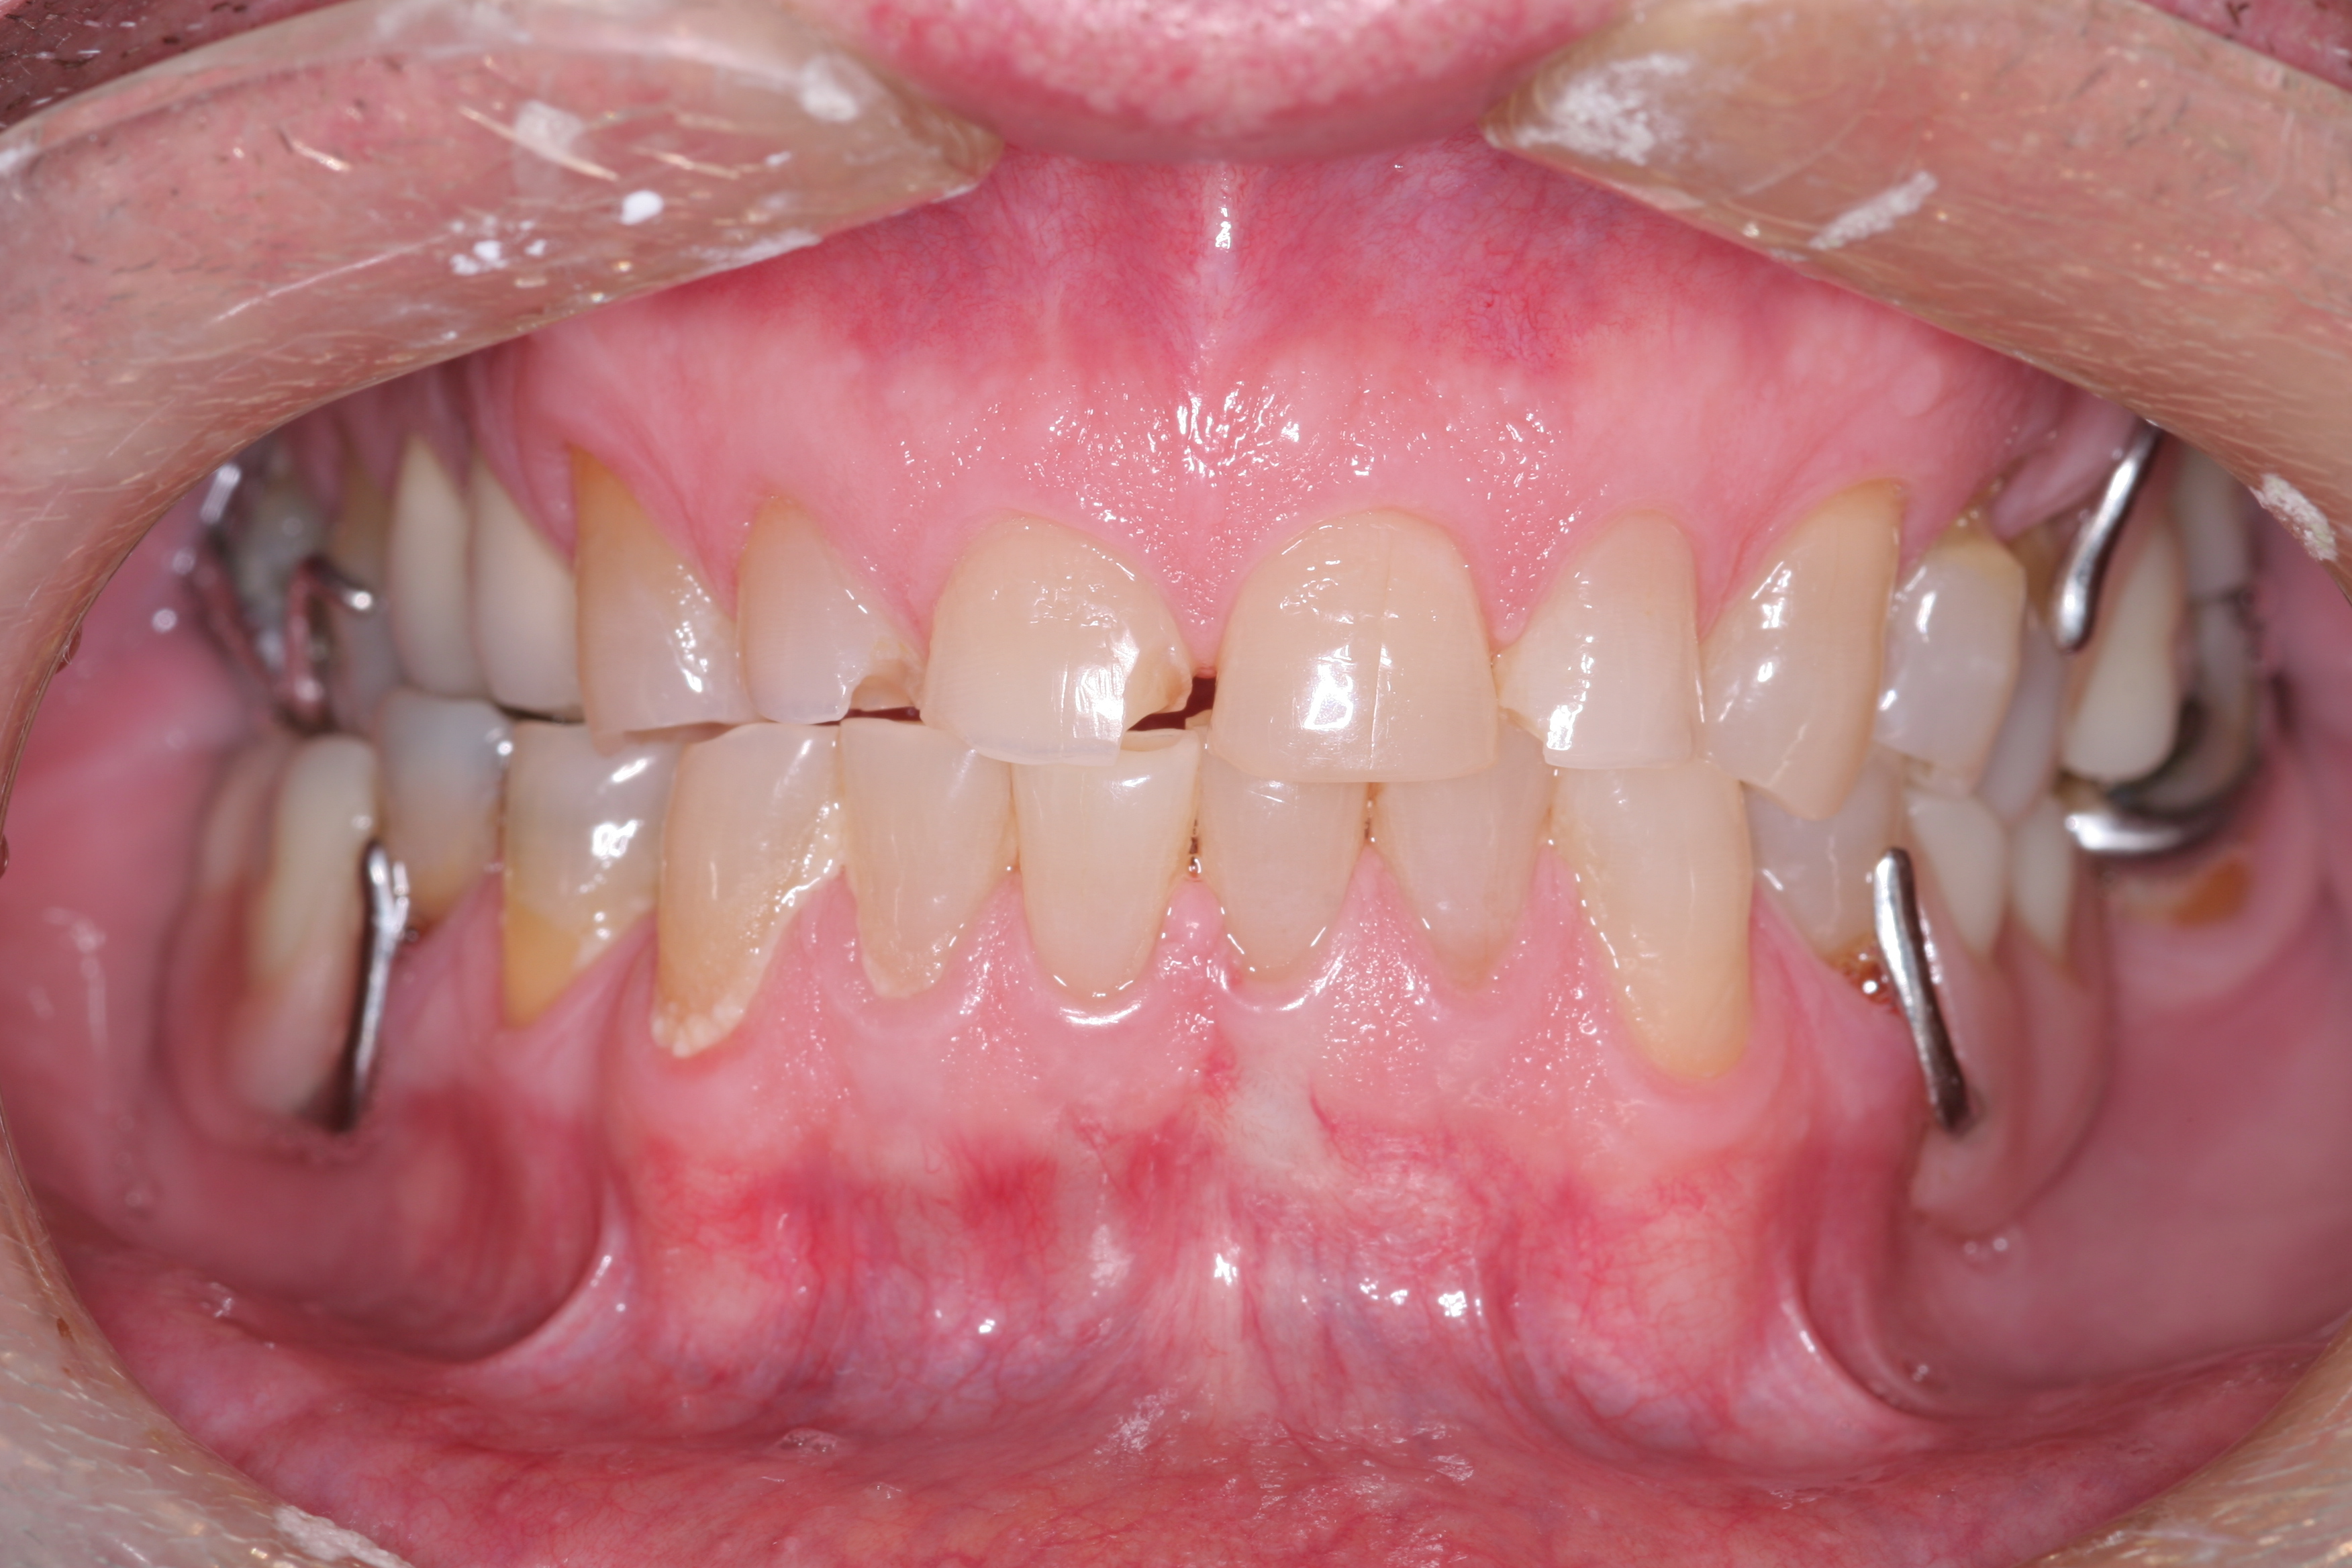

(11.) A patient presented with advanced generalized wear of her anterior teeth, and was displeased with their overall appearance because of their color and wear.

Figure 11

(12.) A patient presented with advanced generalized wear of her anterior teeth, and was displeased with their overall appearance because of their color and wear.

Figure 12

A patient presented with advanced generalized wear of her anterior teeth (Figure 10 and Figure 11). She was displeased with their overall appearance because of their color and wear (Figure 12). A complete examination was performed, revealing instability in her temporomandibular lateral poles bilaterally, sore muscles of mastication, advanced wear, a CR/MIP discrepancy, and loss of her anterior guidance due to the wear. Although the topic is beyond the scope of this article, the patient was also screened for possible sleep apnea. This included an evaluation of the Mallampati score, previous sleep therapy evaluation or treatment, snoring history, an evaluation of her neck size, her weight status, and the presence of the tonsils and their size. In every case, if this clinician suspects airway obstruction to be playing a role in tooth wear issues, the patient is referred to a sleep physician. The patient in this case displayed few apnea risk factors, and the patient’s anterior wear facets fit together like a “lock and key” pattern seen in parafunctional activity. Splint therapy was initiated to stabilize the joints and muscles. A repeatable CR position was verified through load testing. At this point diagnostic models, photographs, a CR bite record, and a facebow were taken and recorded.